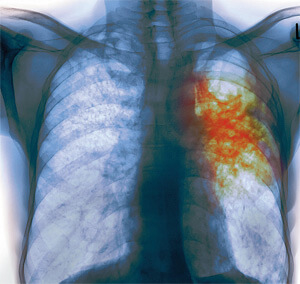

У Держсанепідслужбі розповідають, що захворіти на туберкульоз може кожен, незалежно від віку і статі. Захворювання викликається специфічними збудниками – мікобактеріями і характеризується ураженням легень та інших органів. Заразитися можна від інфікованої людини повітряно-крапельним шляхом. Одна хвора людина може інфікувати за рік 10-15 осіб: «Також краплини слини хворого осідають на різні поверхні, висихають. У такому вигляді мікобактерії туберкульозу можуть зберігатися тривалий час – до 12 місяців, а потім під час прибирання приміщення підніматися у повітря з пилом та потрапляти в організм здорової людини, – пише Файне місто Тернопіль.